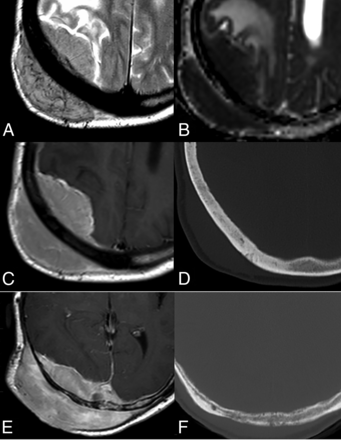

Primary DLBCLs of the CNS, EBV-negative. A–C: Usual deep, periventricular, corpus callosum, and midline location (A); a rare location in the posterior fossa (B); and exceptional in the spinal cord (C). D–G: Parenchymal lesions with associated characteristic leptomeningeal (D), subependymal (E), and perivascular (arrow, F) enhancement patterns. Histologic hematoxylin-eosin stain (original magnification ×20) shows highly cellular, perivascular accumulation of lymphoma cells (G). H–J: Mass lesion with ill-defined infiltrative (H) or well-defined expansive (I) margins. Hyperattenuated lesions on NCCT (J). K–N: Deep T2 hypointensity of a lesion (K) with a T2-blackout effect at b = 1000 image (L) but a low signal of actual diffusion restriction on the ADC map (M). Ki-67 proliferation index by immunohistochemistry (original magnification ×20) exceeding 90% (N).

Notably, these lesions are frequently hyperattenuating on NCCT,2,5⇓-7,11 which is important to keep in mind because CT is the first-line radiologic examination and suspicion at this point may lead to corticoid avoidance (Fig 1). If administered, corticoids can complicate subsequent imaging and histologic diagnosis.2,3,12

Regarding specific tumor MR imaging features, lymphoma typically appears hypointense on T2WI with marked diffusion restriction on DWI. Nevertheless, a T2-blackout effect consisting of a persistent hypointensity on b = 1000 images due to very low T2 signal may lead to misinterpretation. Thus, ADC map hypointensity might be more reliable than b = 1000 hyperintensity in assessing actual diffusion restriction.2,5⇓-7,11 NCCT hyperattenuation, low T2 signal, and diffusion restriction correlate with high cellularity on histology, with Ki-67 proliferation indexes usually above 90% (Fig 1).13